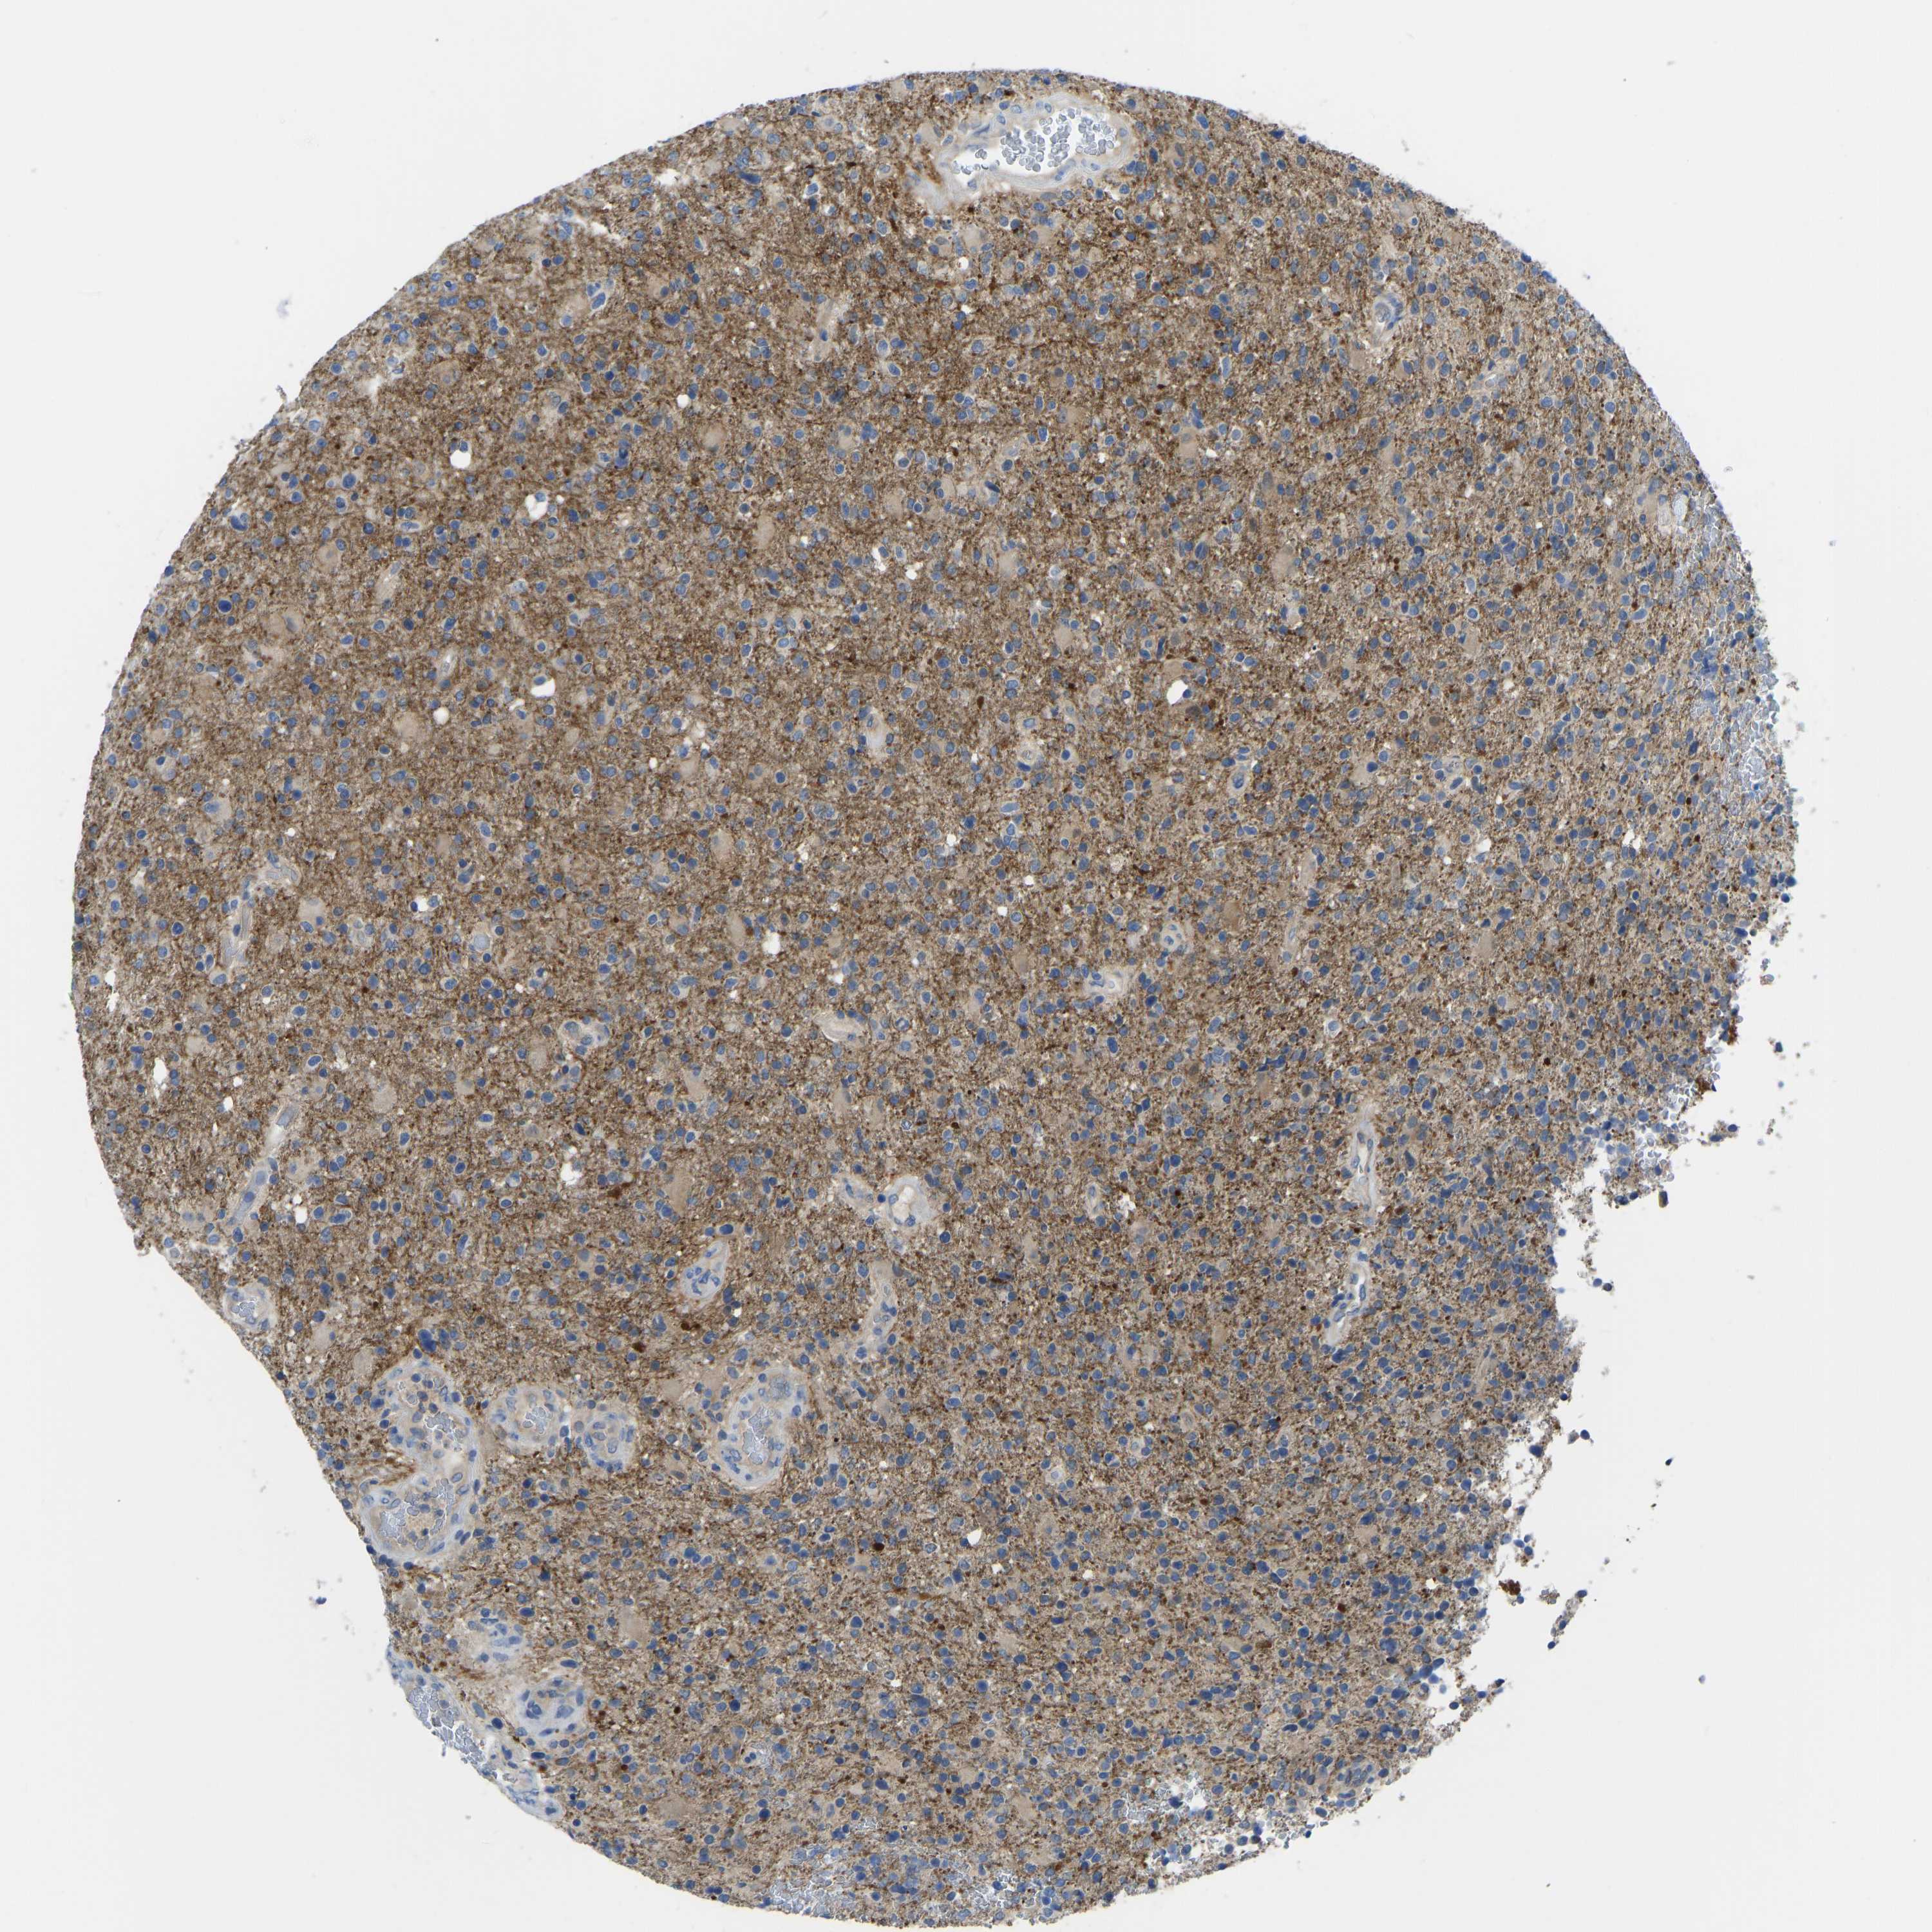

GLIOMA - Protein expressioni

A mouse-over function shows sample information and annotation data. Click on an image to view it in a full screen mode. Samples can be filtered based on level of antibody staining by selecting one or several of the following categories: high, medium, low and not detected. The assay and annotation is described here.

Note that samples used for immunohistochemistry by the Human Protein Atlas do not correspond to samples in the TCGA dataset.

Antibody stainingi

Antibody staining in the annotated cell types in the current human tissue is reported as not detected, low, medium, or high, based on conventional immunohistochemistry profiling in selected tissues. This score is based on the combination of the staining intensity and fraction of stained cells.

Each image is clickable and will lead to virtual microscopy that enables deeper exploration of all samples and also displays staining intensity scores, fraction scores and subcellular localization as well as patient and tissue information for each sample.

Antibody HPA012778

Antibody CAB018581

Staining

High

Medium

Low

Not detected

Intensity

Strong

Moderate

Weak

Negative

Quantity

>75%

75%-25%

<25%

None

Location

Nuclear

Cytoplasmic/membranous

Cytoplasmic/membranous,nuclear

Glioma, malignant, High grade

Glioma, malignant, Low grade